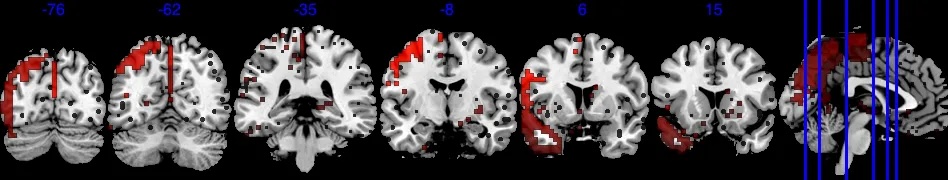

To define the analysis mask, we recall the definition of observed proportion (OP) at location to be , where is the set of all observed locations for individual . We define the group analysis mask as , i.e., the area where each voxel has at least 50% observed data. As shown in Figure 2, the group analysis mask with completely observed data (purple area) covers significantly less area compared to , which has at least 0.5 observed proportion (blue area). In the complete observed data, large portions of the brain regions are missing, notably including the orbitofrontal cortex, the inferior temporal cortex, and the amygdala—regions crucial for emotion processing. In particular, the mask with complete observed data contains only 52 out of the 110 regions in the Harvard-Oxford atlas.

After applying a common mask with an observed proportion of 0.5, we end up with that contains voxels. The image outcomes are standardized across subjects, i.e. where is the original image for subject location , is the sample mean, and SD[M(s)] is the standard deviation of . For each region, we apply the Matérn kernel function but with different and parameters (6), to account for the different smoothness of each region. Both and are determined through grid search so that the empirical covariance of and the estimated covariance by the Matérn kernel have the smallest difference in Frobenius norm. The number of bases is chosen so that the cumulative summation accounts for 90% of the total summation of all eigenvalues, hence we have a total number of . In Section 4.4.1, we provide a sensitivity analysis when the cutoff is based on 92% of the total summation.

In addition, Figure 6 shows results equivalent to those in Figure 3, but with the selection indicator applied simultaneously to both the main effect and the interaction effect. As shown in Figure 6(b), the posterior of in model (10) is driven by both and . The regions exhibiting strong negative effects of do not fully align with the regions showing , in contrast to the original results in Figure 3(b). Therefore, if the primary interest is in the main exposure variable , such as age in our analysis, we recommend applying exclusively to this primary effect to achieve a more accurate selection of activation regions.

Since the gender variable is binary with female being 0 and male being 1, the interpretation for is that comparing to the female subjects, one standard deviation (s.d.) increase in age for male subjects is associated with -s.d. of change in the image intensity. The boxed green area in Figure 6(c) and Figure 6(b) identifies one active area where has a negligible effect, but has a large effect size, indicating that this area is associated with the differences of male’s age-brain intensity association compared to female. For example, one s.d. increase in male’s age is associated with at least 0.01 s.d. increase in brain signal intensity compared to the female baseline in this green-boxed area. On the other hand, Figure 6(d) also identifies areas where one s.d. increase in male’s age is associated with at least 0.01 s.d. decrease in brain signal intensity compared to the female baseline. The area in the green box spans several brain regions in the right hemisphere, including Right lateral occipital cortex, superior division, Right insular cortex, Right middle temporal gyrus, posterior division, and Right frontal operculum cortex. They jointly integrate information from multiple modalities and detect behaviorally relevant stimuli. The negative in Figure 6(d) spans over Right parahippocampal gyrus, posterior division, Right temporal fusiform cortex, posterior division, Left temporal fusiform cortex, posterior division, Left temporal pole. They jointly process and integrate vision and semantic information and are related to contextual and memory functions.